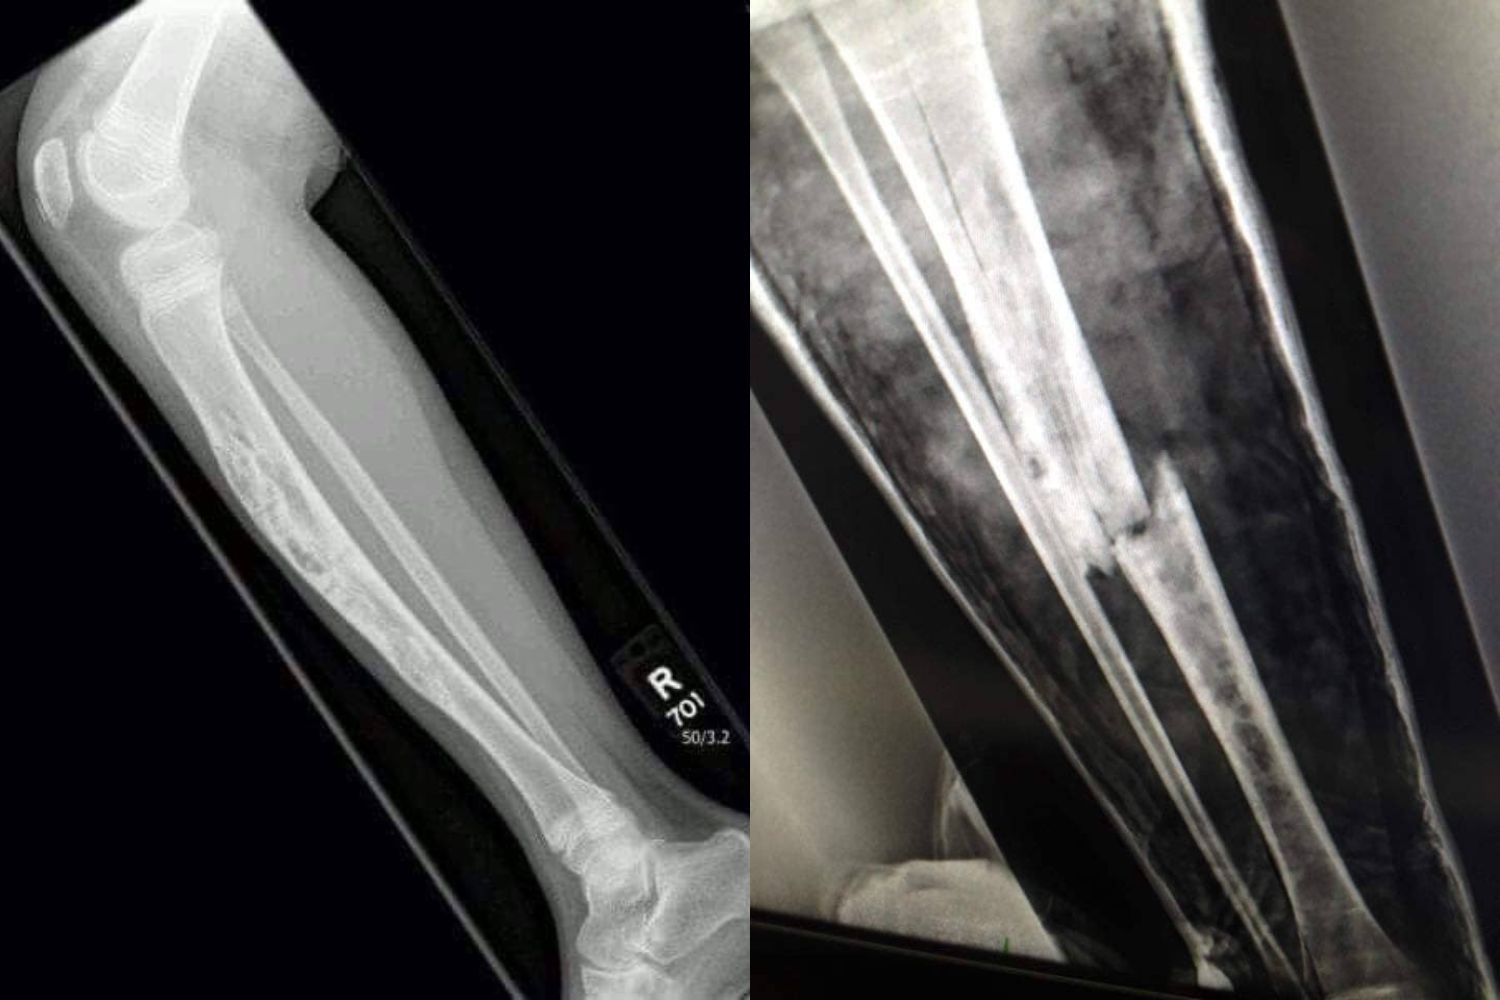

When I was 8 years old, I was diagnosed with a rare bone cancer called adamantinoma after a freak incident in my garden. While the cancer was confined to my right leg, it meant the bone was extremely fragile and that I couldn't bear weight on it.

A sound I had been taught to fear my entire life. I knew instantly… I had broken my diseased leg.

After an emergency trip to A&E and repositioning surgery a few days later, I was told the break was so severe that I would never walk again. I became bedbound, confined to a hospital bed in my living room.